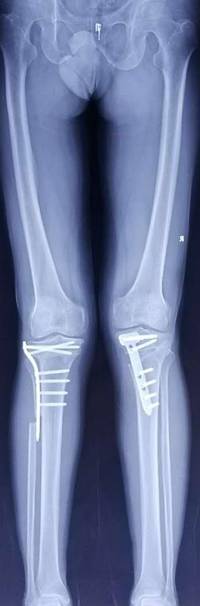

胫骨高位截骨治疗膝关节骨关节炎

优点:创伤小,疗效确切,适合生活方式活跃的年轻患者。

关节镜下微创治疗胫骨平台髁间嵴骨折

优点:创伤小,康复快。